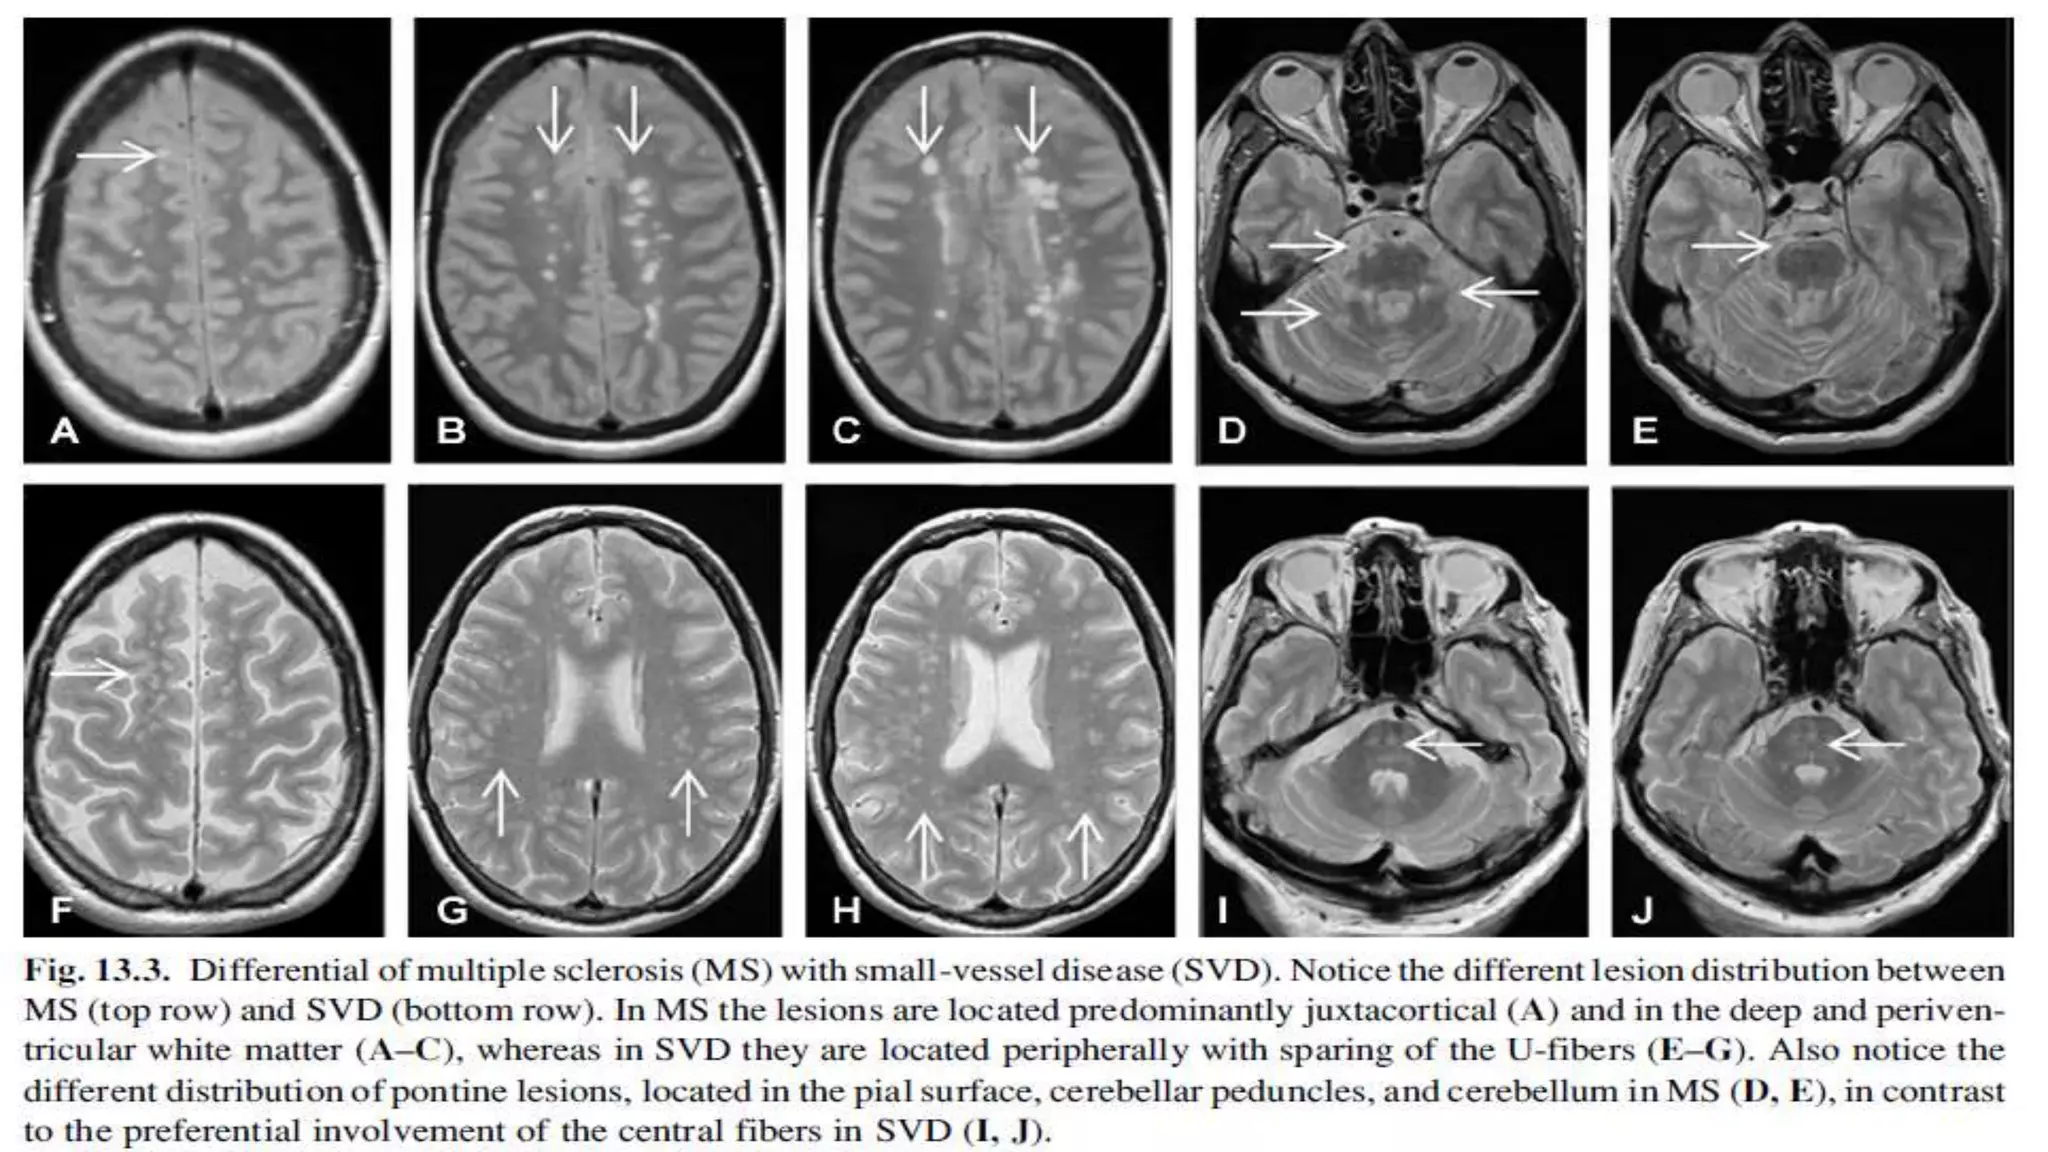

3 of 4 1 Gd+ or 9 T2-hyperintense lesions if there is no enhancing lesion  At least one infratentorial lesion  At least one juxtacortical lesion  At least 3 periventricular lesions MRI criteria dissemination in space Barkhof et al criteria